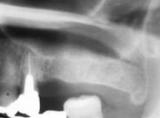

GBR | ||

| 骨の量が少なくても、骨を再生しインプラントを植立することが出来ます。 インプラントのために骨再生する事をGBRといいます。 |

【術前】 |

【術後】 |